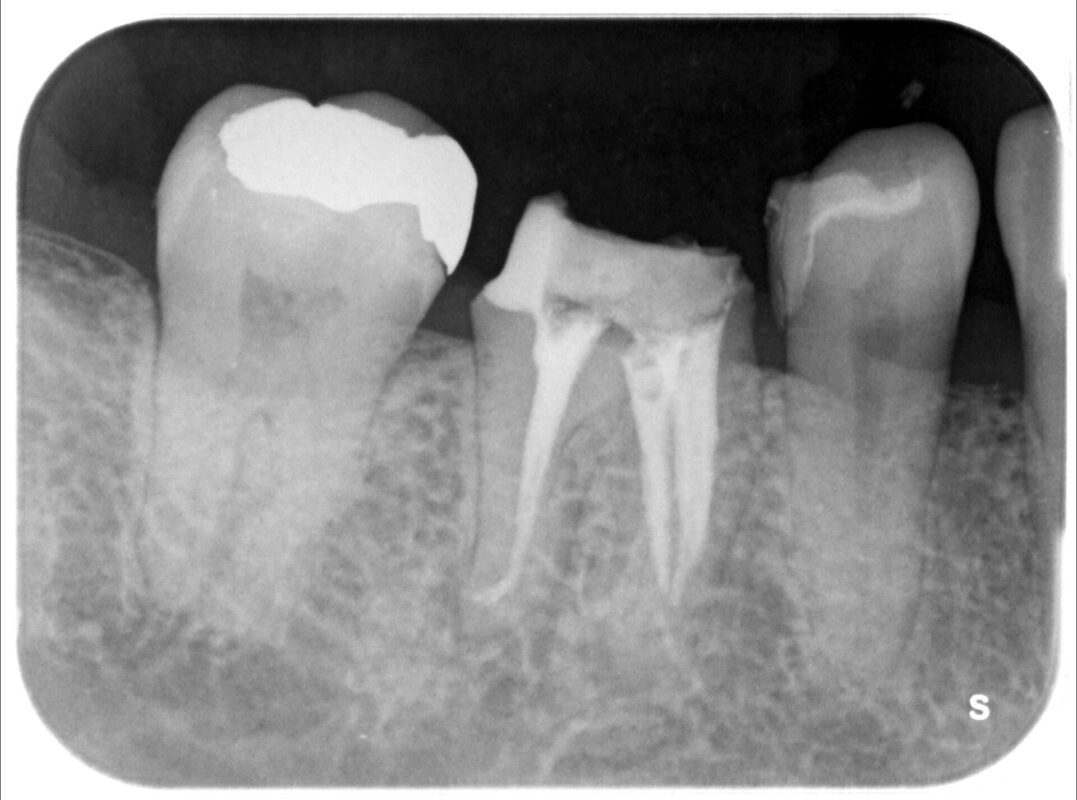

根管充填完了

レントゲン的には2本折れていると思ったのですが、実は3本折れて残留していました。

2時間以上かかって3本とも除去できました。

遠心根は先に根管充填終わっています。